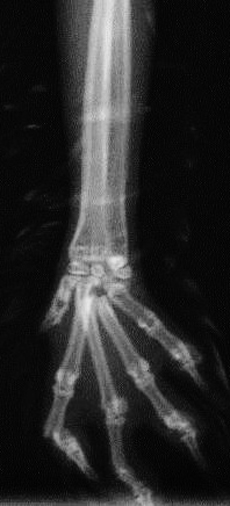

ウサギの脛骨骨折

骨折時レントゲン写真

整復手術後のレントゲン写真

骨折時のレントゲン写真

手術中の写真

プレートとスクリューを用いて骨折を整復します